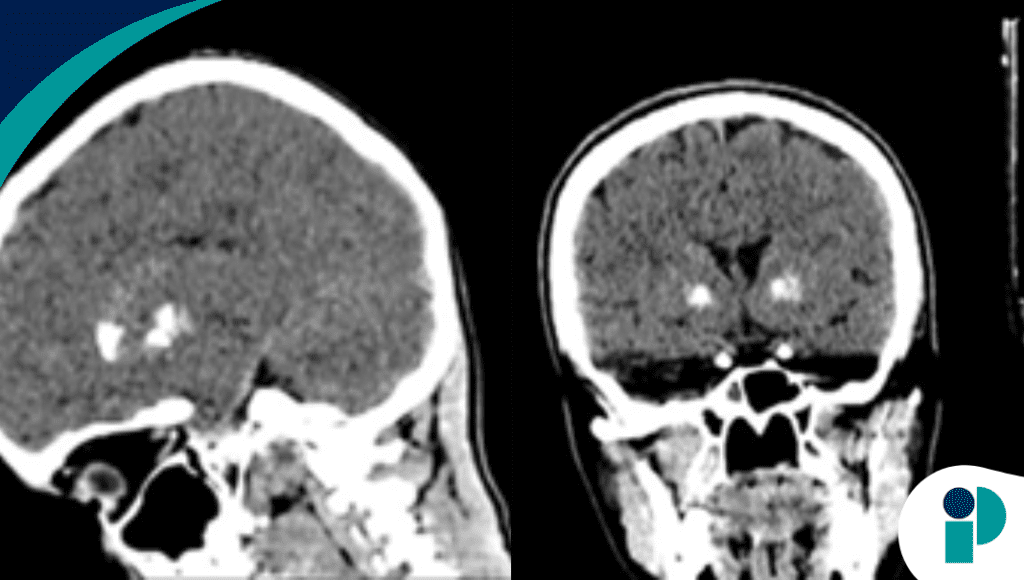

La enfermedad de Fahr puede ser un hallazgo silencioso hasta que una situación clínica común saca a la luz un marcado patrón de calcificación intracraneal. En este caso, un hombre de mediana edad acudió tras una caída con trauma craneal menor, sin síntomas neurológicos iniciales relevantes, pero la tomografía computarizada de cráneo reveló hallazgos radiológicos llamativos: calcificaciones bilaterales y simétricas en ganglios basales, tálamo y corteza cerebral.

Estos depósitos calcificados, típicos de enfermedad de Fahr familiar, sugieren una alteración metabólica o neurodegenerativa subyacente, incluso en ausencia de manifestaciones clínicas evidentes al momento del accidente. Los autores destacan que estos hallazgos no se vincularon directamente al trauma craneal, sino que fueron un descubrimiento incidental que permitió confirmar el diagnóstico de una enfermedad poco común.